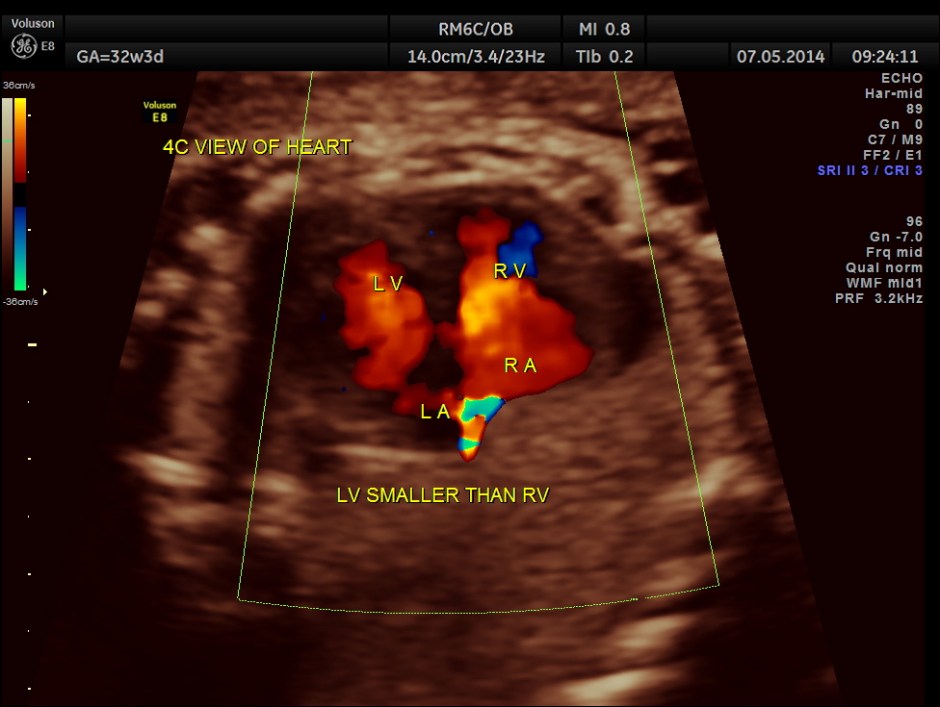

The 4 chamber view shows enlarged RA and RV and a confluence venous chamber behind the left atrium.

LA & LV appear to be smaller than RA & RV.

The situs appeared to be normal.

A transverse vessel is seen below the left atrium and is not seen to drain into the left atrium.

No definitive pulmonary vein draining into the left atrium could be made out . A common transverse vessel was seen beneath the left atrium . The LA & RA were smaller than the RA. Similarly the Aorta and the aortic arch were smaller than the pulmonary artery and the ductal arch due to the increased flow in the right side.